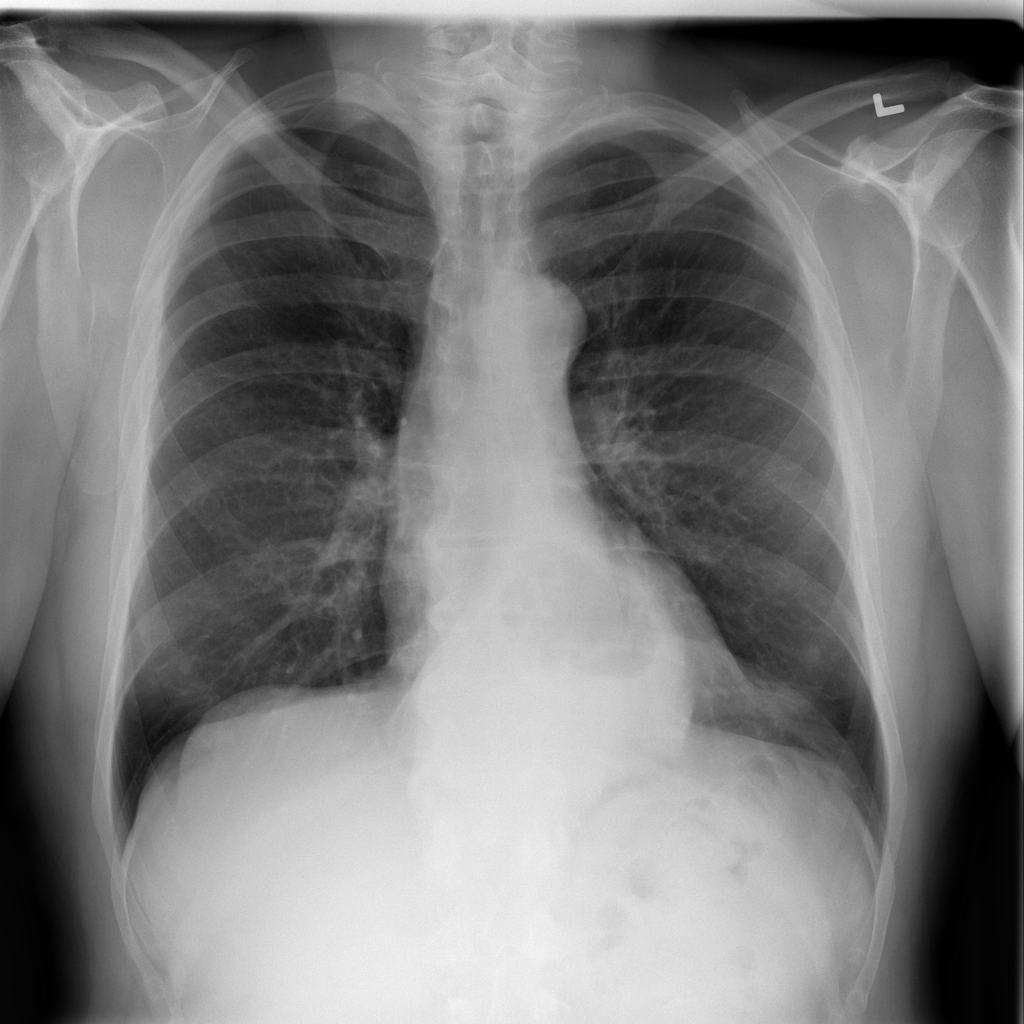

PAT-C048 · IMG-001Hernia

PAT-C048 · IMG-001

PA